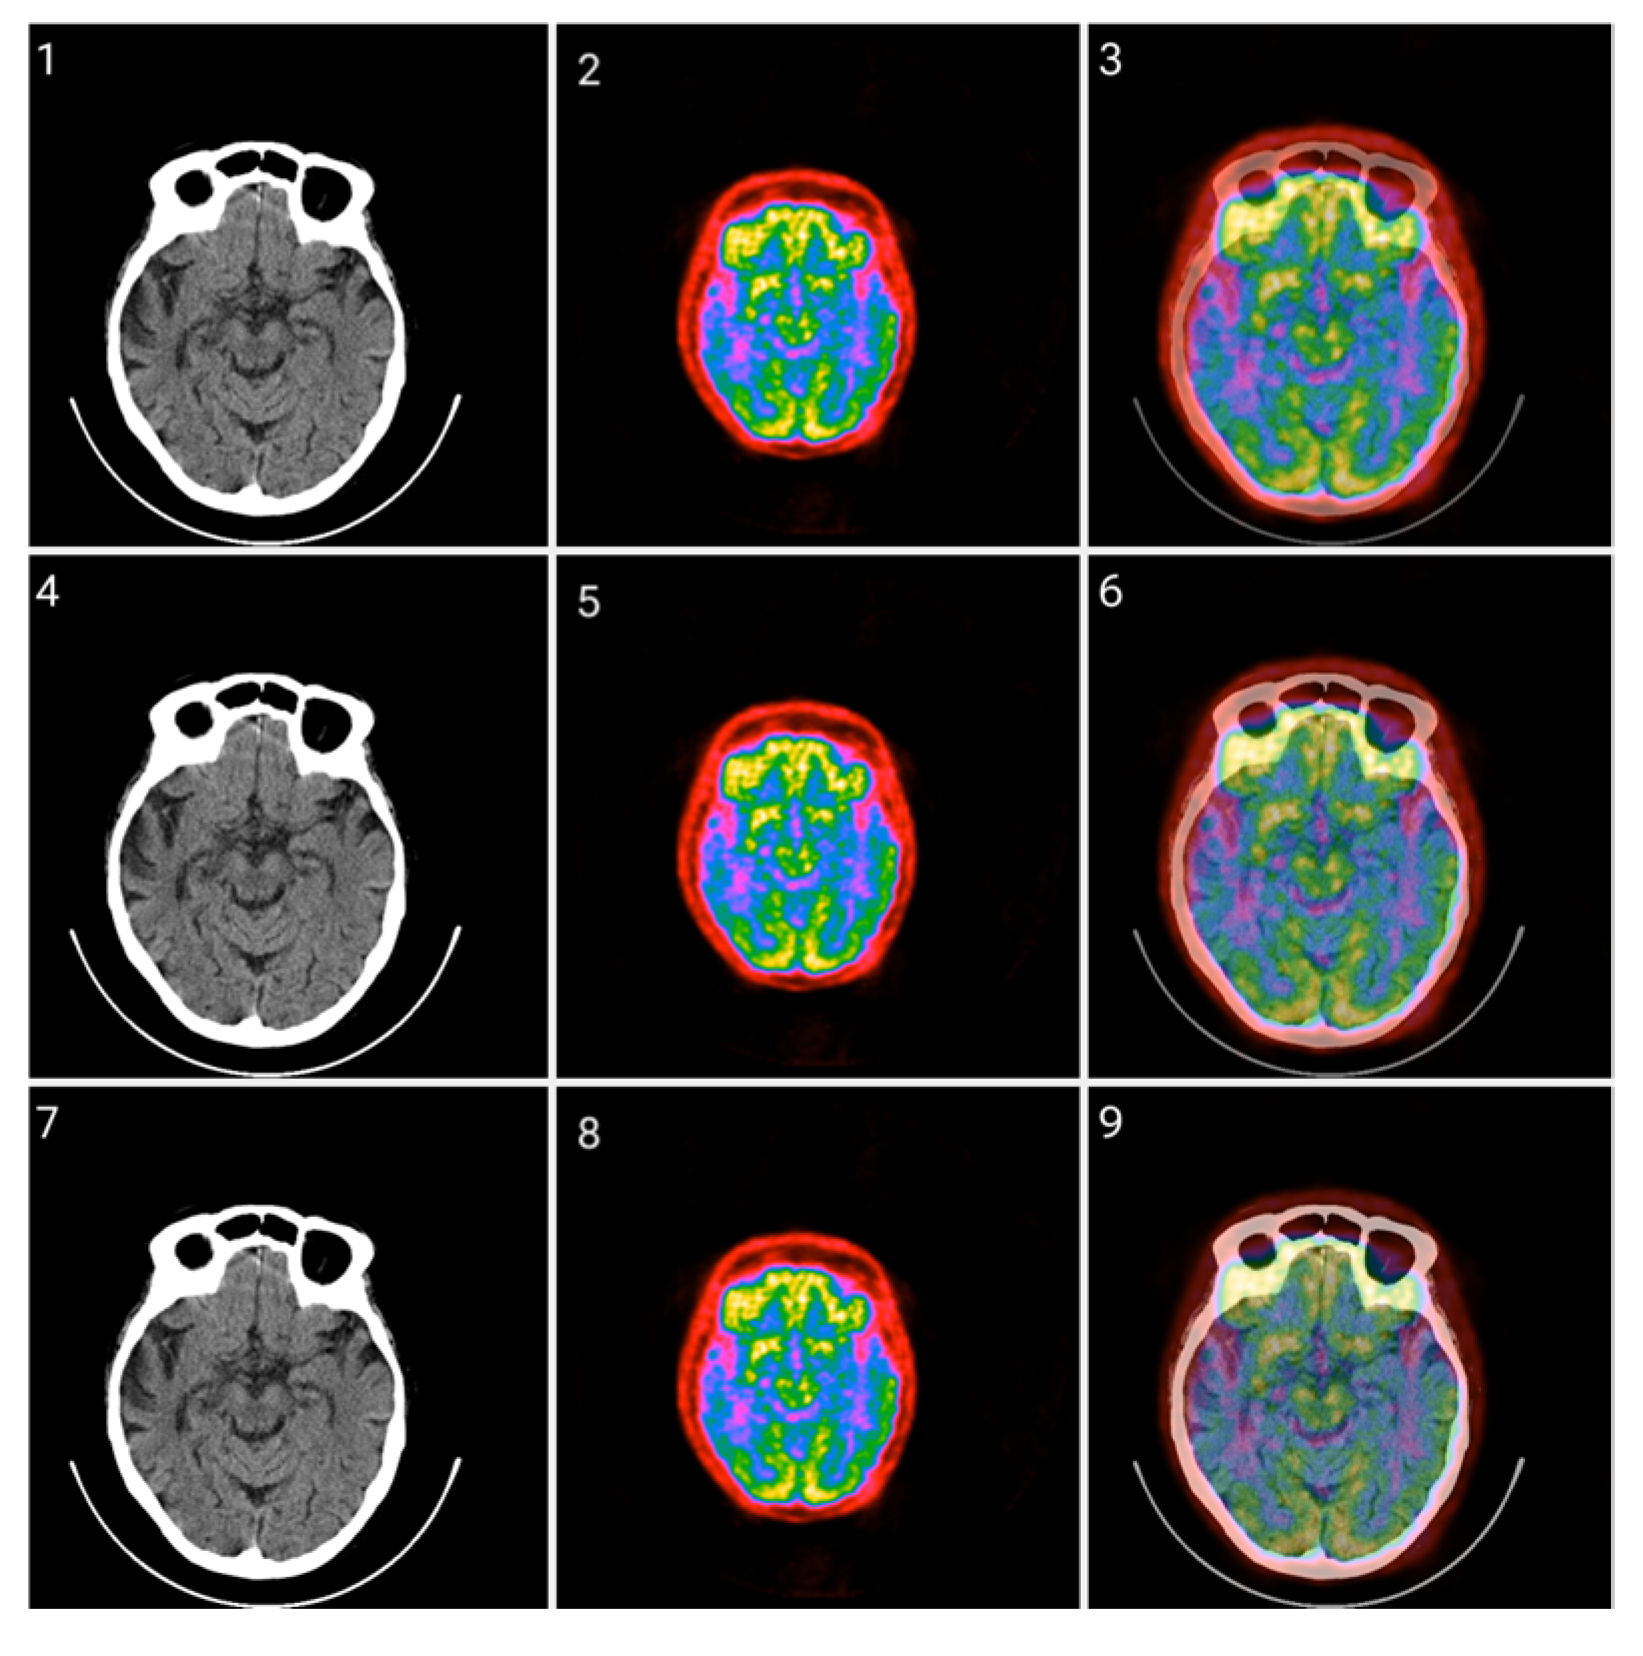

The proposed Colormap Folding method is carried out using only white, black, and colors. Gray shades are left out of the method because the classical CT grayscale images will be fused with PET images that have undergone colormap folding. The fusion was evaluated using different percentage ratios and the results are presented in Figure 12, Figure 13 and Figure 14 for different folds.

Figure 12.

Fusion of CT and PET images at different ratios. Images 1, 4, and 7 present a standard windowed CT image. Images 2, 5, and 8 present the corresponding PET image after Colormap Folding by 1 fold. Images 3, 6, and 9 present the results of fusing the CT and PET images at different ratios, 35%, 50%, 65% CT with 65%, 50%, 35% PET, respectively.

Figure 13.

Fusion of CT and PET images at different ratios. Images 1, 4, and 7 present a standard windowed CT image. Images 2, 5, and 8 present the corresponding PET image after Colormap Folding by 2 folds. Images 3, 6, and 9 present the results of fusing the CT and PET images at different ratios, 35%, 50%, 65% CT with 65%, 50%, 35% PET, respectively.